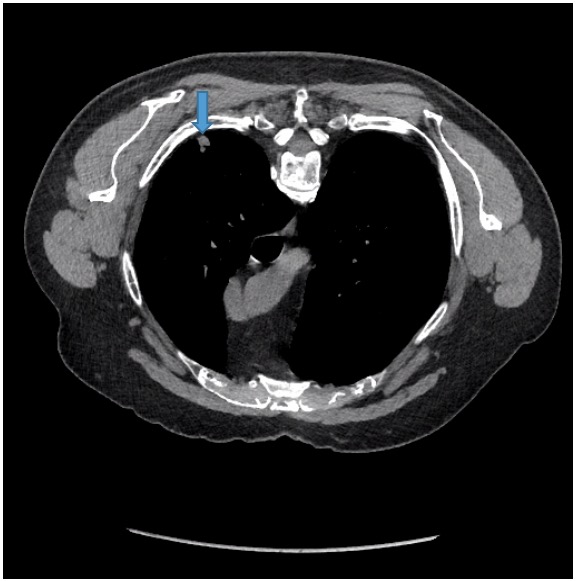

CT image showing centrilobular nodular opacities in the left lower lobe

CT image showing centrilobular nodular opacities in the left lower lobe Spiculated Nodular Opacities By definition, the solitary pulmonary nodule (spn). Most lung nodules are benign (not cancerous). Most are benign, but a small number represent early lung. Rarely, pulmonary nodules are a. Depending on their attenuation in ct imaging, lung nodules are categorized in three different types: Pulmonary nodules are small, focal, radiographic opacities that may be solitary or multiple. Pulmonary nodules are. Spiculated Nodular Opacities.